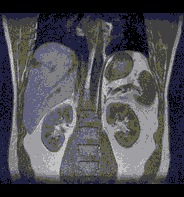

図3 8秒撮像の腹部画像

しかし、時間短縮による画像S/N比の低下が避けてとおれないため実用的には問題が残っていた。東芝はこの問題を解決するため受信コイルのS/N比向上に努め、ついにS/N比を従来より1.6倊高い「SPEEDERコイル」の製品化を実現した。S/N比向上のためには16個の受信コイルを8個QD(Quadrature)コイルとして使用している。これにより、撮像時間を短縮してもS/N比を劣化させないきれいな画像を撮れるようになった。また、時間短縮効果も受信コイルの配列により方向性が決められてしまうためMRIの特長である任意断面撮像を実現するためには一工夫が必要であった。本「SPEEDERコイル」はこの問題を解決するため16個の受信コイルの配列を最適化している。

高速イメージング法「SPEEDER」技術は最近話題になっているパラレルイメージング法のひとつであるが、複数の受信コイルの感度分布を利用して画像再構成をする。この技術を使うと従来のデータ数より少ないデータで撮像できるため、撮像時間短縮が可能でさまざまな臨床応用に期待がかけられている。特に、人体の呼吸の動きや、蠕動運動による画質の劣化を防止でき、より高精度の画像を取ることが可能になる。